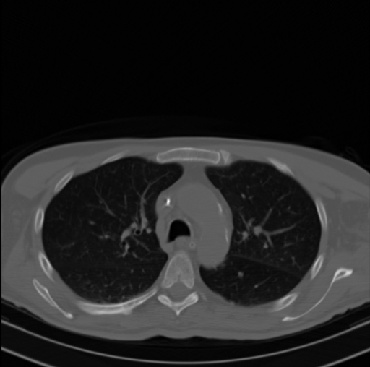

Early and reliable COVID-19 diagnosis based on chest 3-D CT scans can assist medical specialists in vital circumstances. Deep learning methodologies constitute a main approach for chest CT scan analysis and disease prediction. However, large annotated databases are necessary for developing deep learning models that are able to provide COVID-19 diagnosis across various medical environments in different countries. Due to privacy issues, publicly available COVID-19 CT datasets are highly difficult to obtain, which hinders the research and development of AI-enabled diagnosis methods of COVID-19 based on CT scans. In this paper we present the COV19-CT-DB database which is annotated for COVID-19, consisting of about 5,000 3-D CT scans, We have split the database in training, validation and test datasets. The former two datasets can be used for training and validation of machine learning models, while the latter will be used for evaluation of the developed models. We also present a deep learning approach, based on a CNN-RNN network and report its performance on the COVID19-CT-DB database.